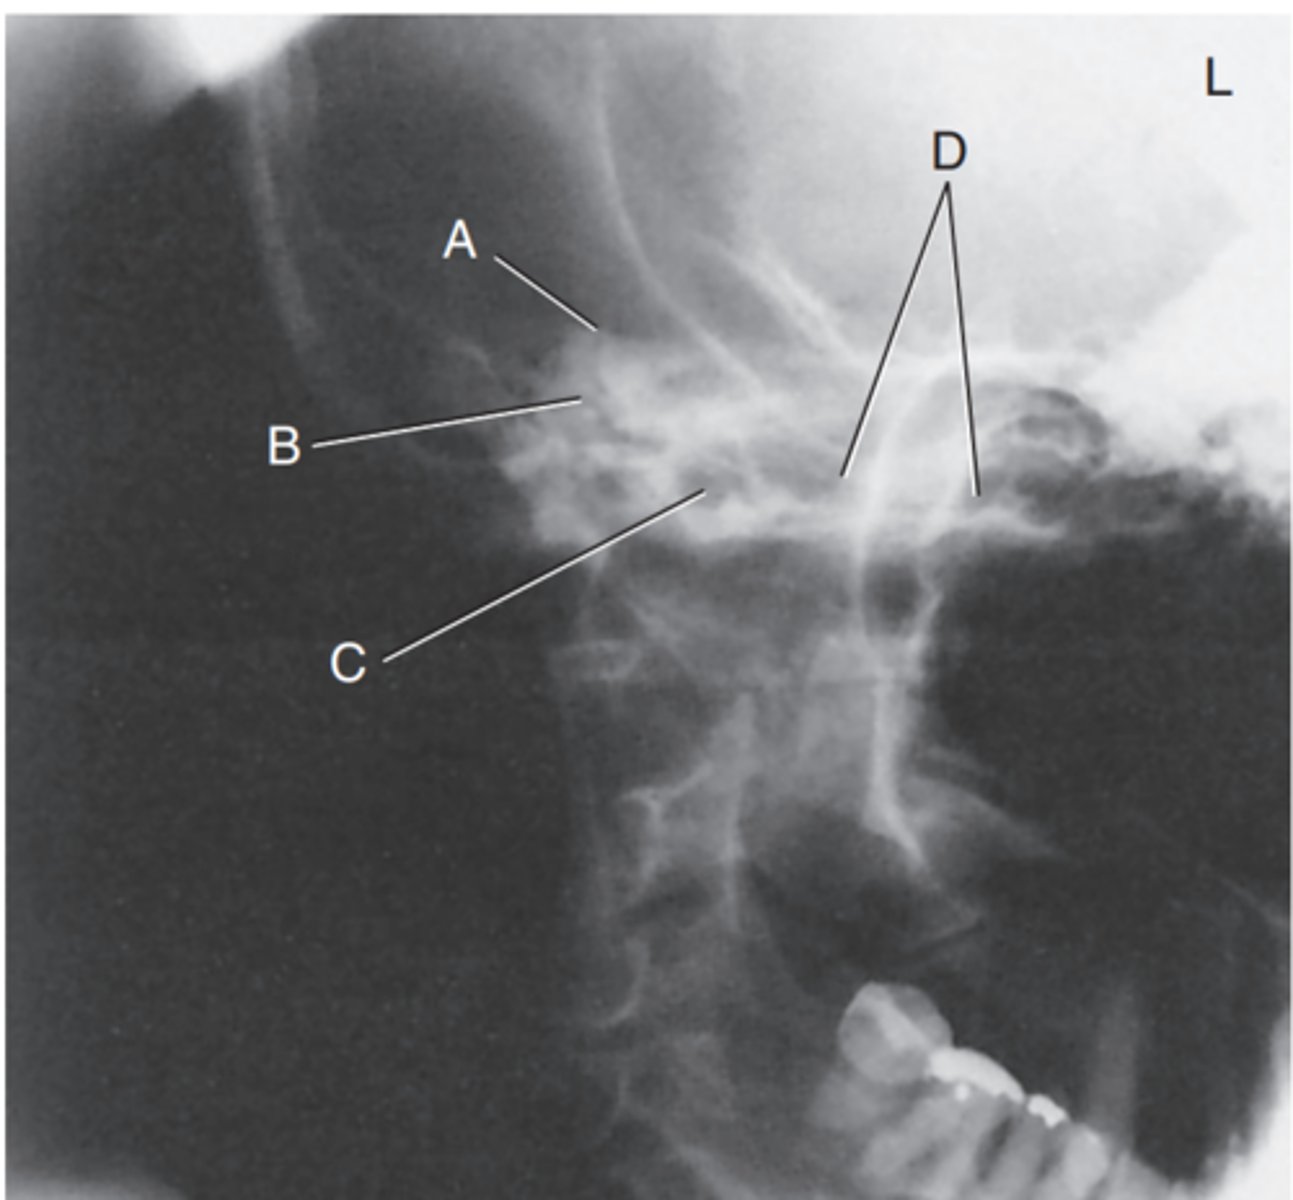

Label A

Mastoid antrum

Label B

Mastoid air cells

Label C

Downside mandibular condyle (just anterior to EAM)

Label D

Upside (magnified) mandibular condyle

Label E